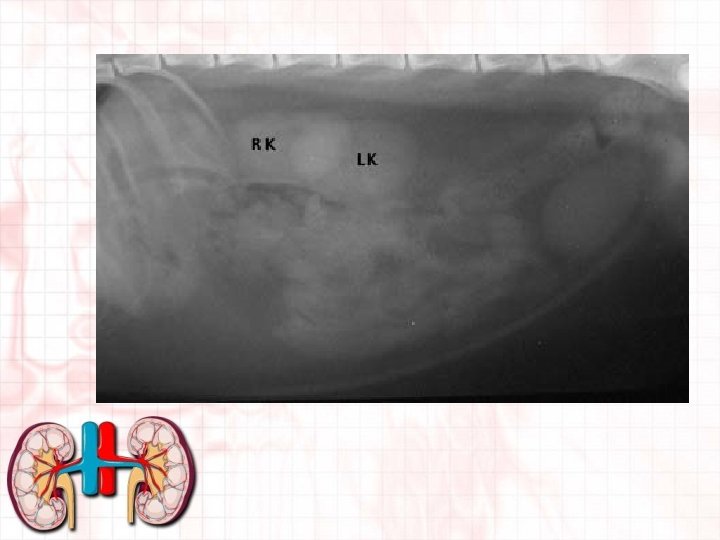

Location of the kidneys • In dorsal part of abdomen • Ventral to and on either side of first few lumbar vertebrae. • In most domestic animals, right kidney is slightly more cranial than left. • Perirenal fat surrounds and helps protect from exertion from other organs. • Are retroperitoneal to the abdominal cavity and so are considered outside abdominal cavity. • Move somewhat with the movement of the diaphragm • Position may vary with species.